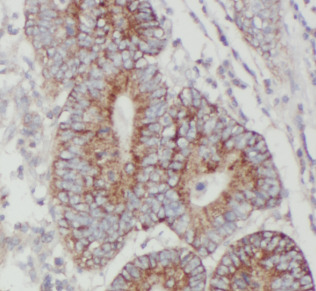

| 验证图片 | Immunohistochemistry of paraffin-embedded human colon cancer tissue slide using FNab04443(JMY Antibody) at dilution of 1:50 Immunofluorescent analysis of HeLa cells using FNab04443 (JMY antibody) at dilution of 1:25 and Rhodamine-Goat anti-Rabbit IgG Jurkat cells were subjected to SDS PAGE followed by western blot with FNab04443(JMY Antibody) at dilution of 1:1000 |